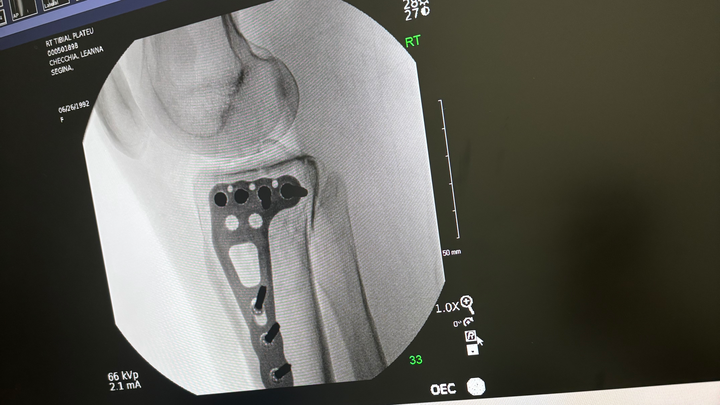

My name is Leanna Checchia. I am reaching out to share my story and seek assistance during an incredibly difficult time. Earlier this month, after enduring years of domestic abuse, I faced what I believe was a final attempt on my life. As a result, I sustained severe injuries and was diagnosed with a tibial plateau fracture, which required emergency surgery. In addition to these physical injuries, I am also coping with Post-Traumatic Stress Disorder (PTSD) stemming from the abuse.